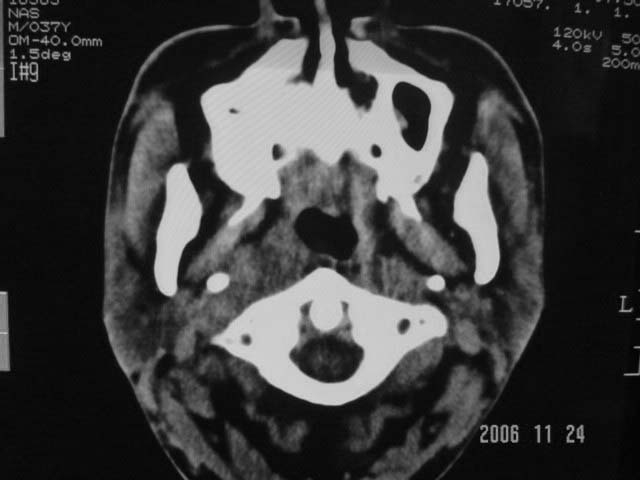

右侧鼻咽部软组织肿块,颅底骨质破坏,右侧颈部淋巴结肿大;诊断:鼻咽ca、右颈部淋巴结转移、颅底侵犯

右侧鼻口咽侧后壁不规则增厚,内可见密度不均匀性椭圆形软组织块影,边界欠清,咽旁间隙尚清.右颈部可见圆形软组织块影,鼻塞、耳鸣3个月,涕中带血2周,颈部可触及肿大淋巴结,考虑鼻咽癌,颈部淋巴转移.

右侧鼻咽部软组织肿块,颅底骨质破坏,右侧颈部淋巴结肿大;诊断:右侧鼻咽ca伴右颈部淋巴结转移、颅底侵犯.

典型右侧鼻咽ca伴颈部淋巴结转移,中颅底骨侵蚀。

右侧鼻咽侧后壁不规则增厚,咽隐窝变钝,咽旁间隙变狭窄,见组织结节影[哨兵征],蝶骨似破坏,蝶窦内充塞软组织影,翼内外肌上分间隙模糊,右颈后三角区淋巴结肿大,右侧乳突增高气房消失。考虑鼻咽癌伴蝶窦侵犯及淋巴结转移,右侧浆液性中耳炎。其他恶性病变待排。

右侧鼻咽癌伴同侧颈部淋巴结转移可能性大.要是有骨窗,能看到更多征象,有助于诊断